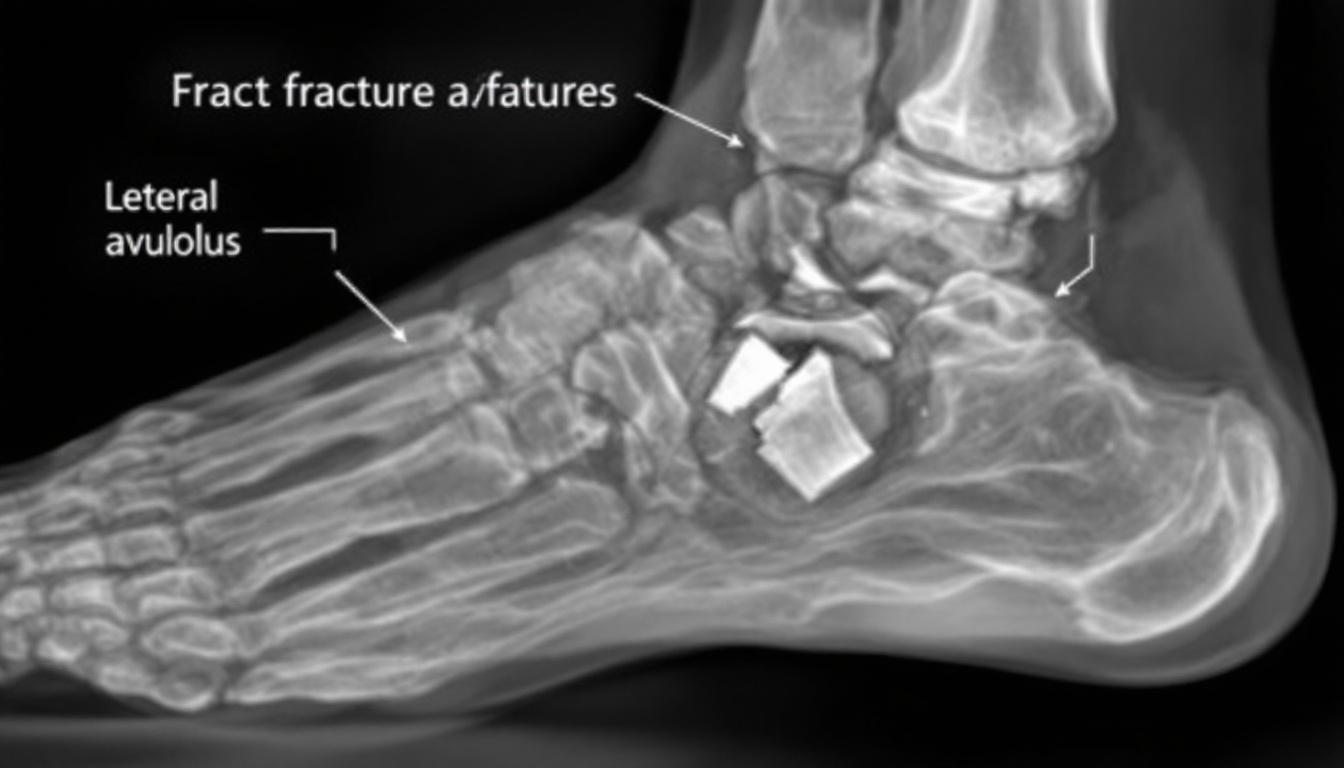

Un déchirement osseux, lié à un traumatisme, entraîne la séparation d’un fragment osseux, souvent au niveau de la cheville. À la différence des entorses, cette lésion implique non seulement les tissus mous mais également les structures osseuses. Ce phénomène se manifeste lors de pratiques sportives ou après une chute sévère, impliquant souvent une torsion brutale ou un impact direct.

La détection rapide et précise est cruciale pour un traitement efficace. Un diagnostic précoce repose sur :

- Examen clinique minutieux pour évaluer la douleur et la stabilité articulaire.

- Radiographie pour repérer les fragments osseux détachés.

- IRM et scanner pour une approche globale, permettant d’analyser les dommages aux tissus mous.

Les technologies d’imagerie ont considérablement évolué, facilitant des diagnostics rapides et précis. Ces informations sont essentielles pour planifier un traitement adéquat, garantissant une récupération osseuse optimale.